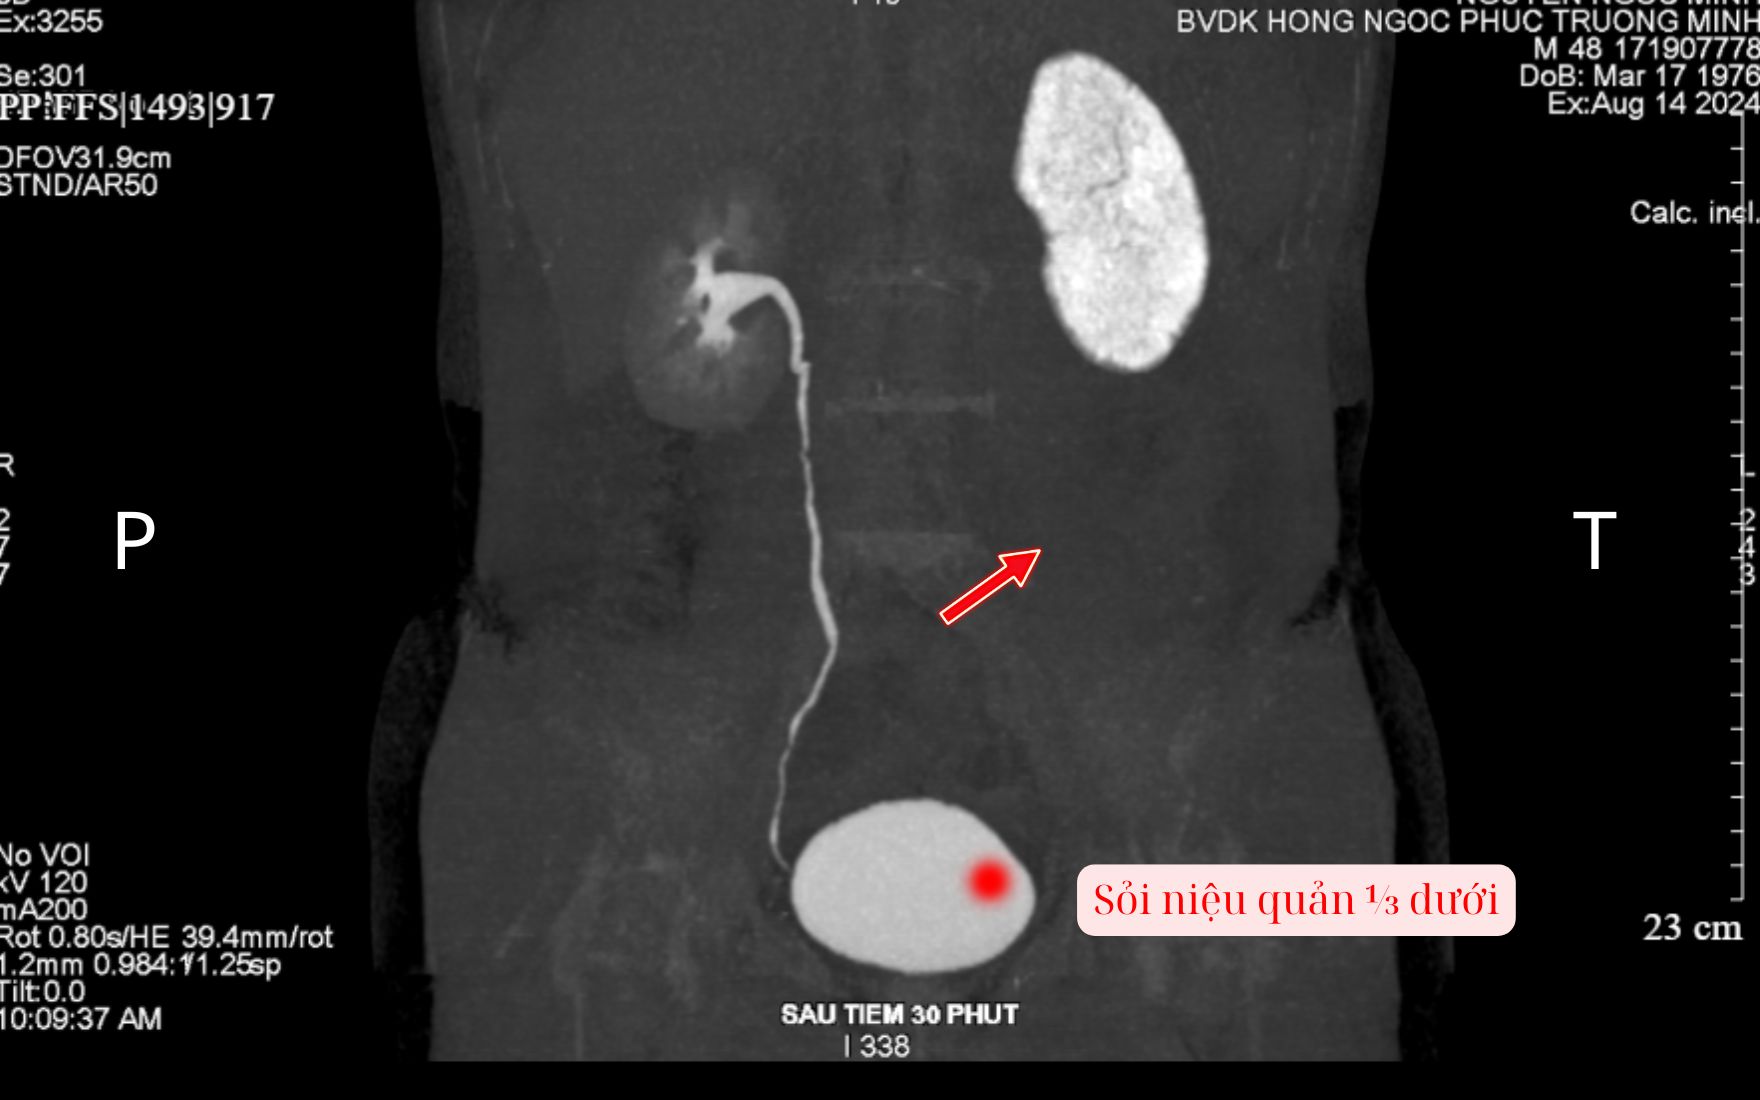

Trường hợp của bệnh nhân N.N.M (35 tuổi) là ví dụ điển hình cho thấy hiệu quả của việc can thiệp kịp thời trong "thời gian vàng". Anh M nhập viện trong tình trạng đau dữ dội vùng thắt lưng trái, kèm biểu hiện đau tức khi tiểu. Kết quả chụp CT cho thấy niệu quản bên trái hoàn toàn không ngấm thuốc cản quang, chứng tỏ đường tiểu đã bị viên sỏi làm tắc nghẽn hoàn toàn, thận trái đã mất chức năng tạm thời.

Niệu quản phải tắc nghẽn, không ngấm thuốc cản quang